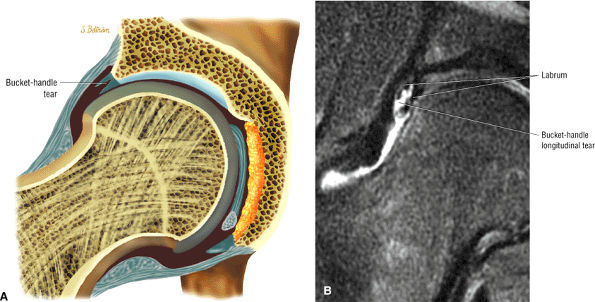

FIGURE 3.33 / Labrum.

labral tear; to avoid this pitfall, suspected labral tears should be confirmed in all three planes.